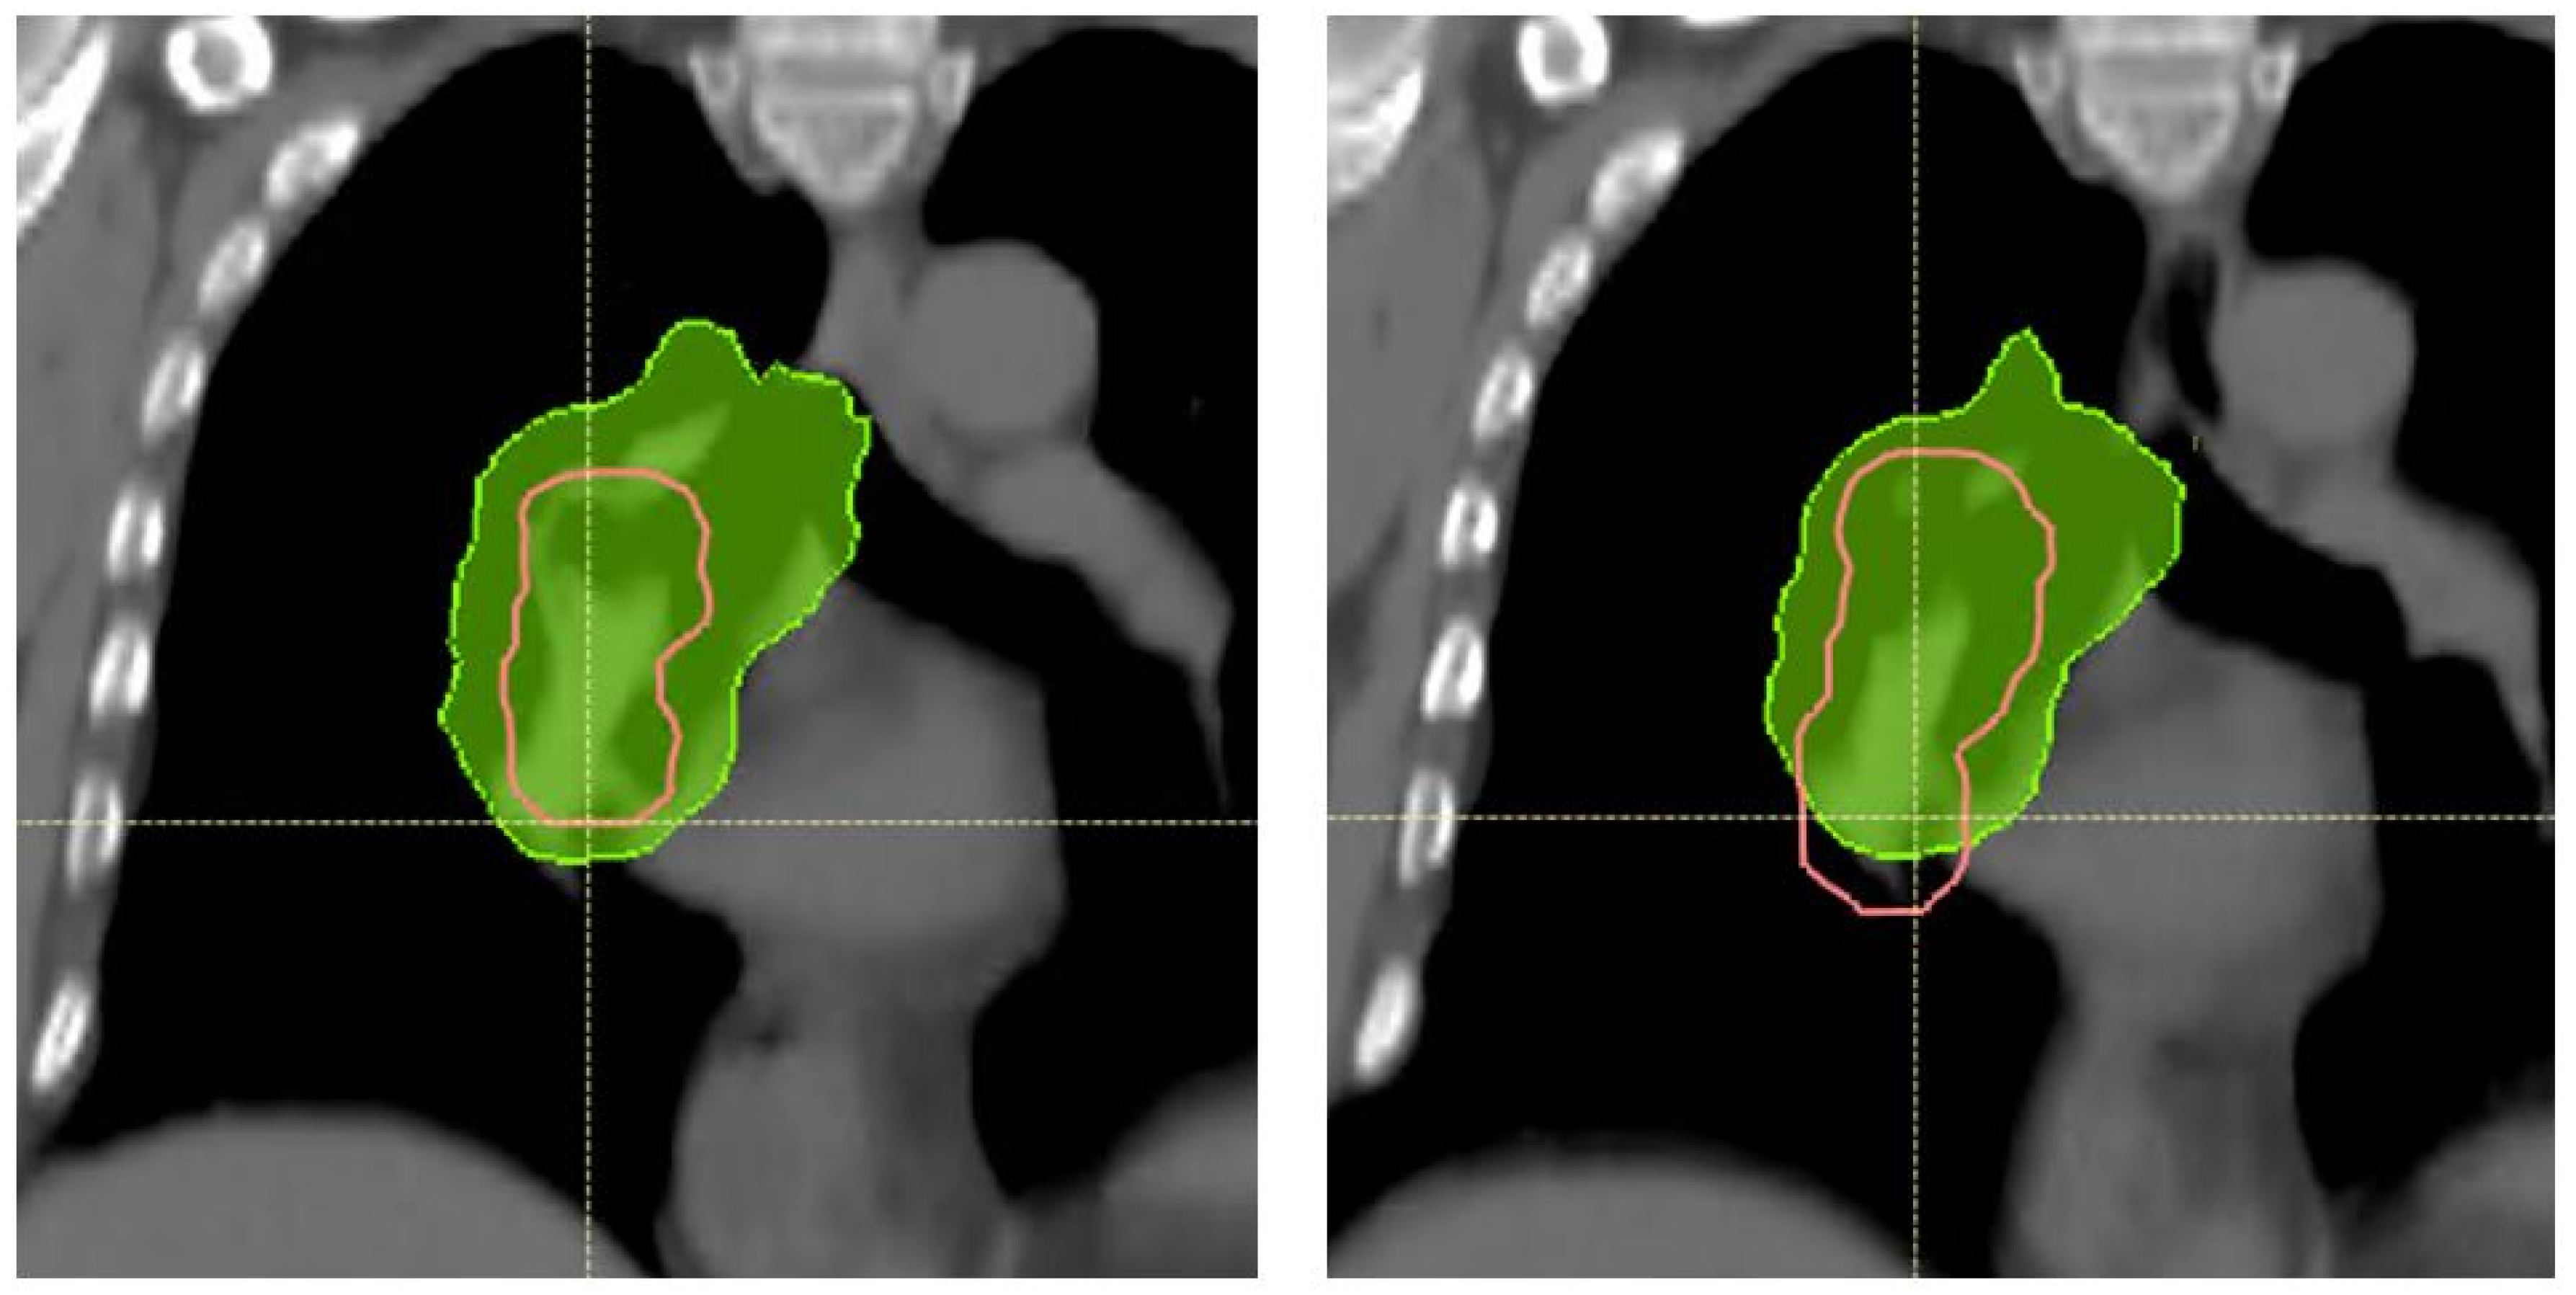

2.3. Robustness Evaluation

3.1. Patient Characteristics and Breathing Motion